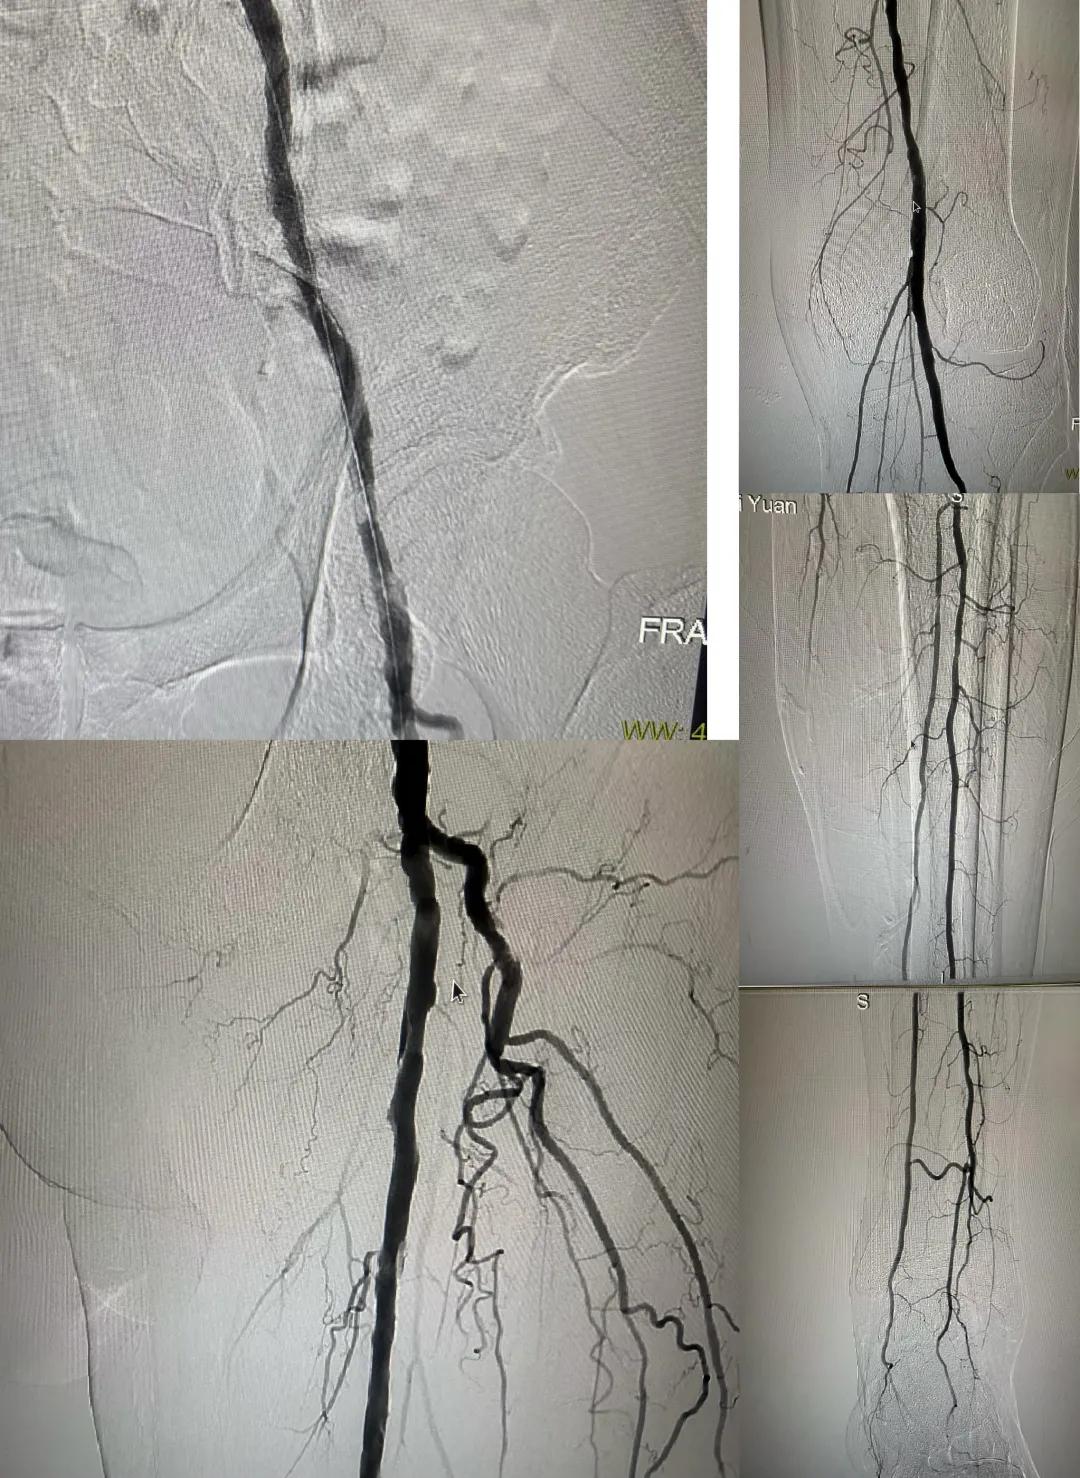

患者,男,73歲,約15天前出現(xiàn)左側(cè)腳面腫痛,間歇性跛行,左足第三足趾壞疽,遂來市中醫(yī)院就診,以“下肢動(dòng)脈硬化閉塞、糖尿病足壞疽、”收住外二科,評(píng)估患者病情后需實(shí)施左下肢球囊擴(kuò)張成形術(shù)。術(shù)中造影見患者左側(cè)髂動(dòng)脈、股淺動(dòng)脈階段性重度狹窄。經(jīng)外周球囊擴(kuò)張術(shù)后,再次造影見股淺動(dòng)脈、髂動(dòng)脈血流通暢,膝下及足部血流速度較前改善。

術(shù)后已疏通血管成像